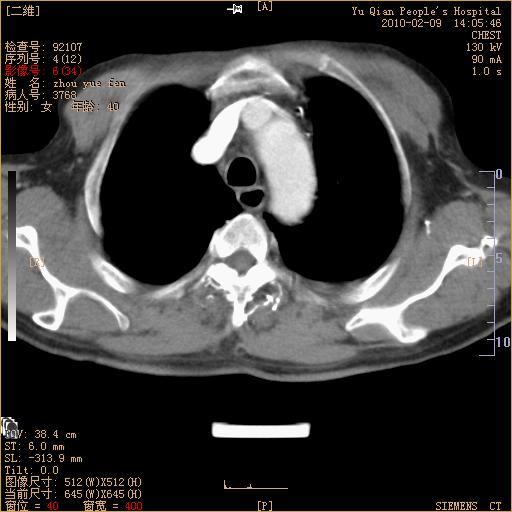

男性,73岁,咳嗽咳血数天,诊为肺ca伴左肺下叶后段阻塞性炎症、肺不张妥否?

左下肺中央型肺癌伴结段形肺不张,左侧胸腔积液,纵隔内见部分增大淋巴结(反应性增生或转移)

左下基底干支气管明显变窄。

左肺下叶基底段支气管狭窄,左肺门增大,左肺下叶团片状病灶。中心型肺癌伴柱塞性炎症可能大,建议支气管镜检查。

左下肺中央型肺癌伴节段性肺不张,左侧胸腔积液,纵隔内见肿大淋巴结

左下基底段支气管变窄。建议进一步纤支镜检查。

1、左肺下叶后基地段肺癌伴阻塞性炎症,左下肺门淋巴结转移。2、左侧胸腔积液。